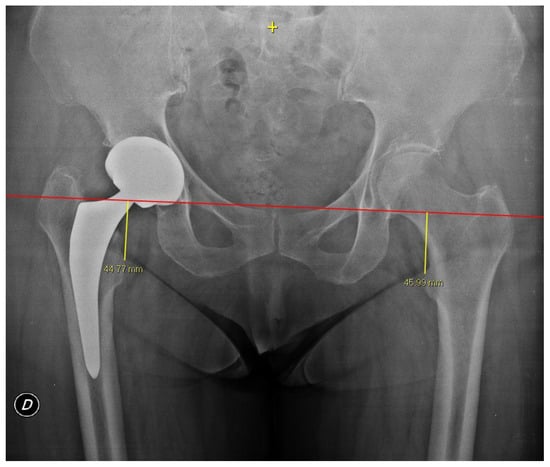

2.4. Radiographic Measurements

3. Results